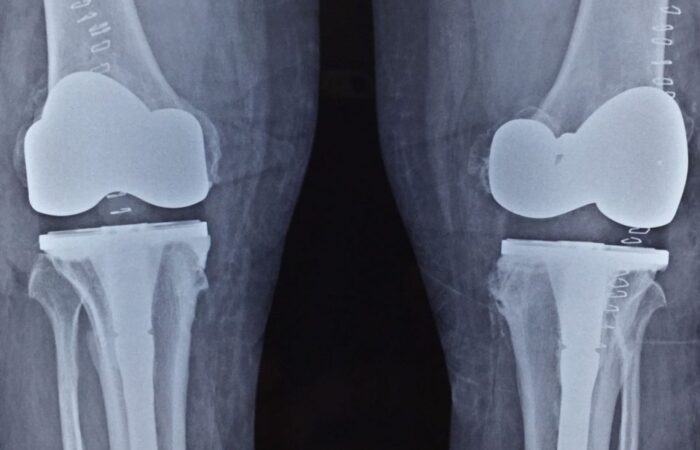

X-rays of patient of bilateral knee replacement in one sitting before and after surgery

Post Operation X-rays

Youngest Patient 39 years old Bilateral Total Knee Replacement done in one sitting.